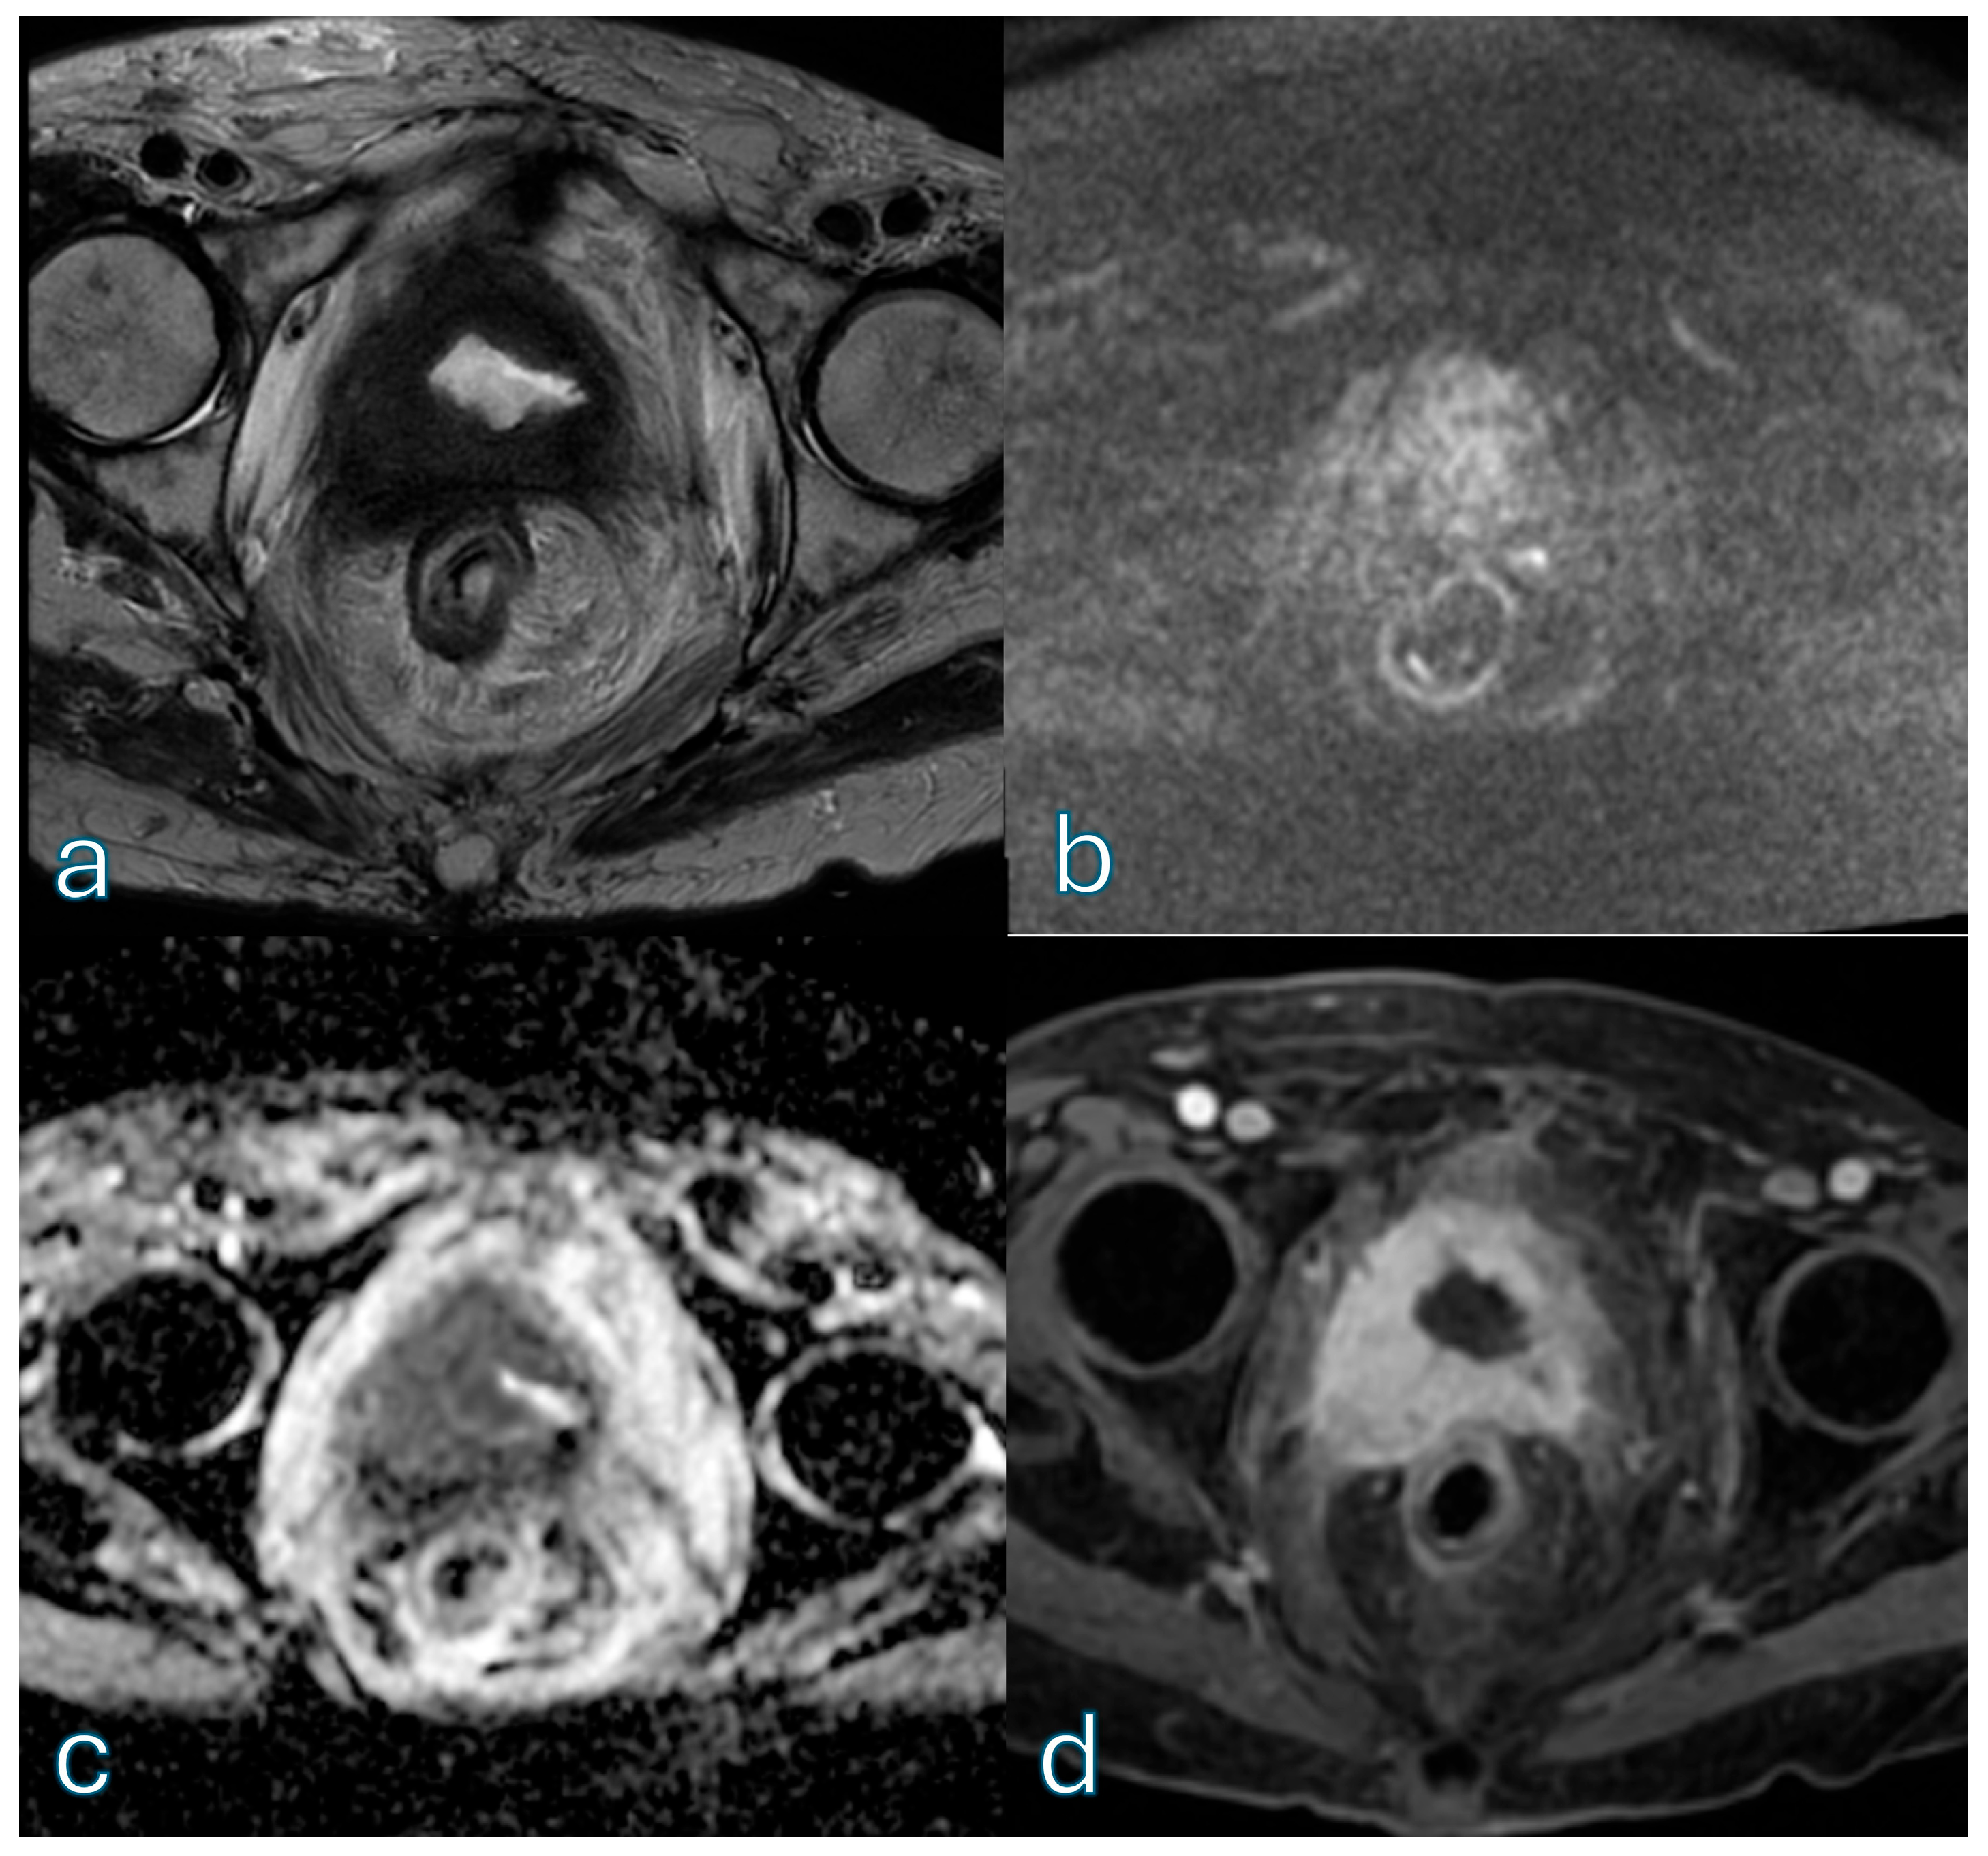

3.7. Histopathological Correlation for Muscle-Invasive Disease

3.8. Post-TURBT Subgroup Analysis